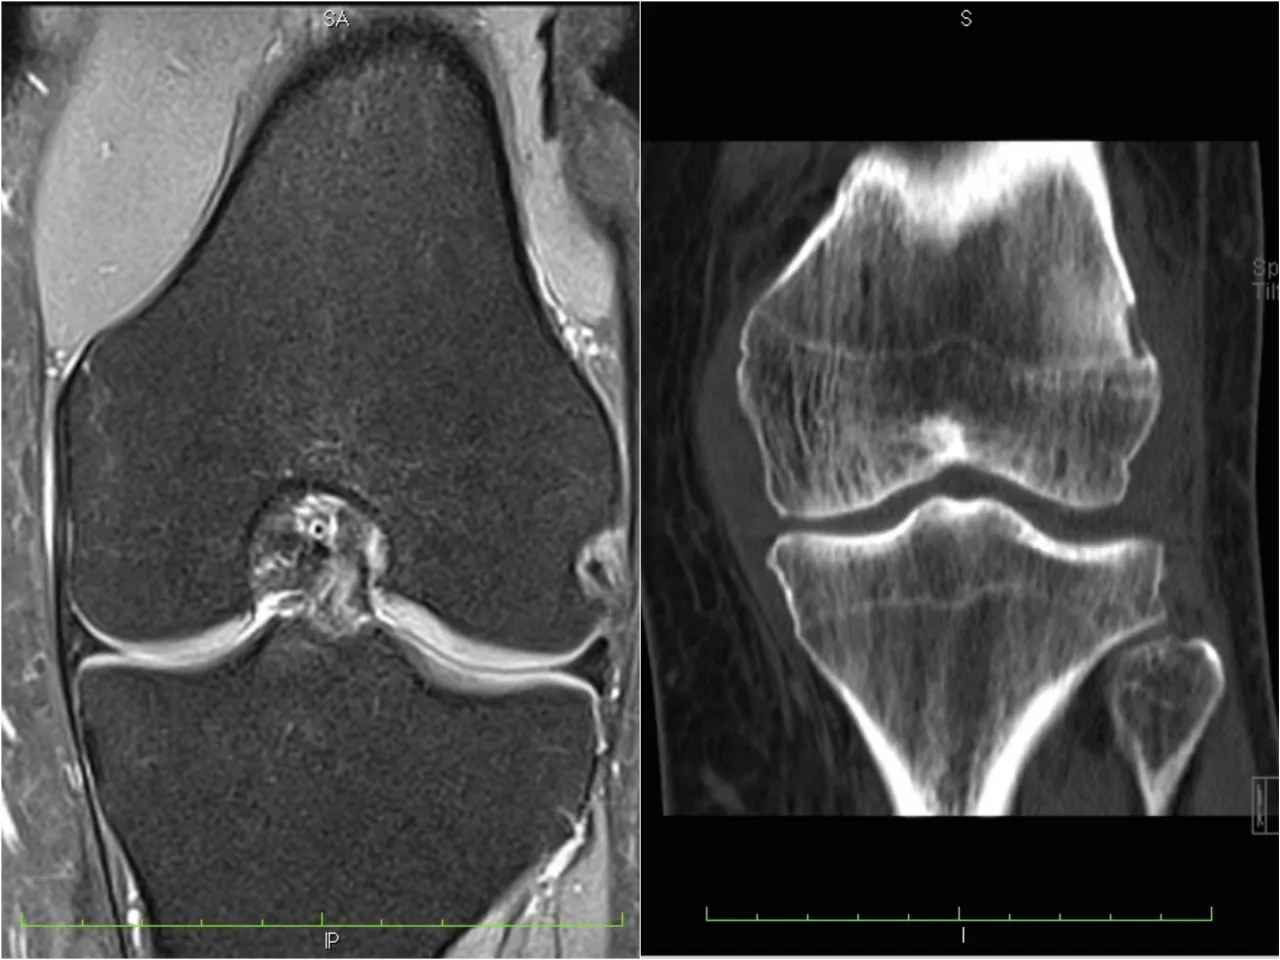

- RTG (rentgen): Podstawowe badanie, pozwalające ocenić strukturę kości, wykryć złamania, pęknięcia, zmiany zwyrodnieniowe czy niektóre nowotwory.

- Tomografia komputerowa (TK): Zapewnia bardziej szczegółowy obraz kości niż RTG, umożliwiając ocenę skomplikowanych złamań, zmian pourazowych czy ognisk nowotworowych.

- Rezonans magnetyczny (MR): Najdokładniejsze badanie do oceny tkanek miękkich (mięśni, więzadeł, chrząstek), ale także szpiku kostnego i zmian zapalnych czy nowotworowych w kościach.